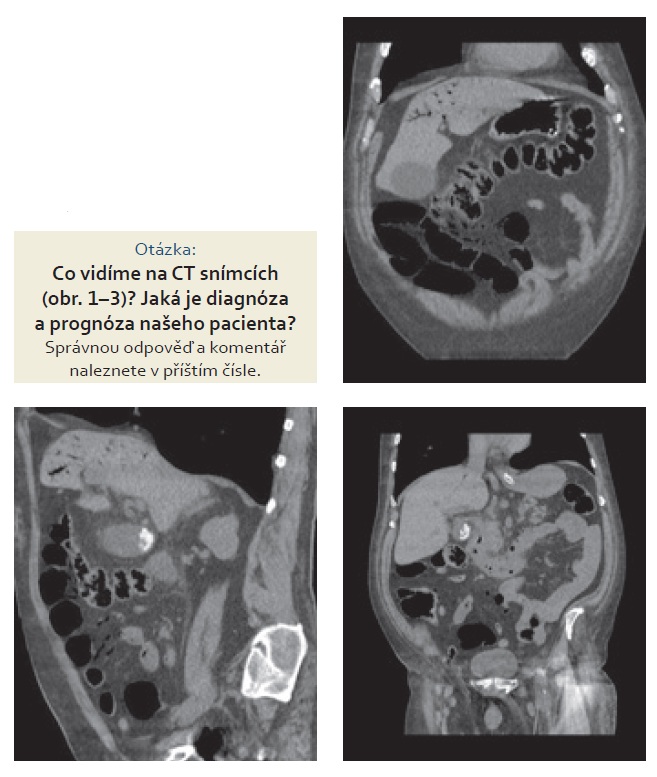

Provedli jsme sonografii břicha s nálezem hydropsu žlučníku se sludge, konkrementy v krčku žlučníku, gastrektazie. Pacientovi jsme zavedli nazogastrickou sondu, která odvedla 1 000 ml stagnačního obsahu. K dalšímu objasnění patologie bylo provedeno nativní CT břicha (zvýšená hladina kreatininu).

Pacienta jsme po konzultaci s radiologem a chirurgem indikovali k operačnímu výkonu.